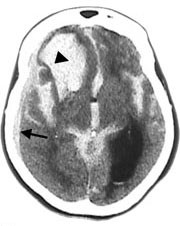

Opplysninger vedrørende cerebral angiografi forelå hos 64 av 70 pasienter med subaraknoidalblødning. Av disse hadde ti (16 %) normalt funn. Til sammen 63 aneurismer ble påvist hos 52 pasienter (81 %). Intracerebral arteriovenøs malformasjon ble påvist hos to pasienter. Hos seks pasienter ble det gjort samtidig funn av henholdsvis fire (n = 2), tre (n = 1) og to (n = 3) aneurismer ved samme undersøkelse. Aneurismer ble hyppigst påvist på a. cerebri media, a. communicans anterior og a. carotis interna (tab 2). Påvisning av blod i subaraknoidalrommet kunne gi indikasjon på lokalisering av aneurismet (tab 2, fig 2, fig 4). Prediksjon for påvisning av lokalisasjon av blødende aneurisme var kun meget god for aneurismer på a. cerebri media, hvor 12 av 13 aneurismer ble lokalisert korrekt. Det var dårligere prediksjon for aneurismer lokalisert til a. communicans anterior og a. carotis interna, med henholdsvis 11 av 18 og fire av ti aneurismer riktig lokalisert. Angiografi var utført hos åtte av ti pasienter med blod i septum pellucidum, og hos samtlige ble det påvist aneurisme på a. communicans anterior (fig 4). For de andre lokalisasjonene var det få observasjoner og lav treffsikkerhet.

Cerebral CT vil ofte kunne gi informasjon om lokalisering av aneurismet som ligger til grunn for blødning (8). Tidligere studier har vist at treffsikkerheten for lokalisering av aneurisme ut fra CT-undersøkelse kun var høy ved ruptur av aneurismer lokalisert til a. communicans anterior og a. cerebri anterior (15, 16). I vår studie fant vi høyest treffsikkerhet når det gjaldt blødning fra aneurisme på a. cerebri media, også med riktig sideangivelse, mens treffsikkerheten med hensyn til blødning fra aneurisme på a. communicans anterior var dårligere. Septum pellucidum-hematom er ansett som et sikkert tegn på aneurisme på a. communicans anterior (8), og dette ble bekreftet i vår studie. Derimot vil ikke alle aneurismer lokalisert til a. communicans anterior blø til septum pellucidum. Enkelte angir at blod i fissura interhemisphærica er et sikkert og hyppig tegn ved aneurismer på a. pericallosa, men dette var ukjent for oss da bildene ble gjennomgått. Lokalisering av blødende aneurisme før radiologisk eller kirurgisk sikring er spesielt viktig når det foreligger flere aneurismer. Multiple aneurismer, vanligvis to eller tre, kan finnes hos 20 – 30 % av pasienter med intrakraniale aneurismer (17). I akutte situasjoner kan det hende at pasientens tilstand ikke tillater den tidsbruk som går med til angiografi. En ”nødoperasjon” er helt avhengig av at CT viser og kan tolkes med størst mulig sikkerhet med hensyn til lokalisasjon.